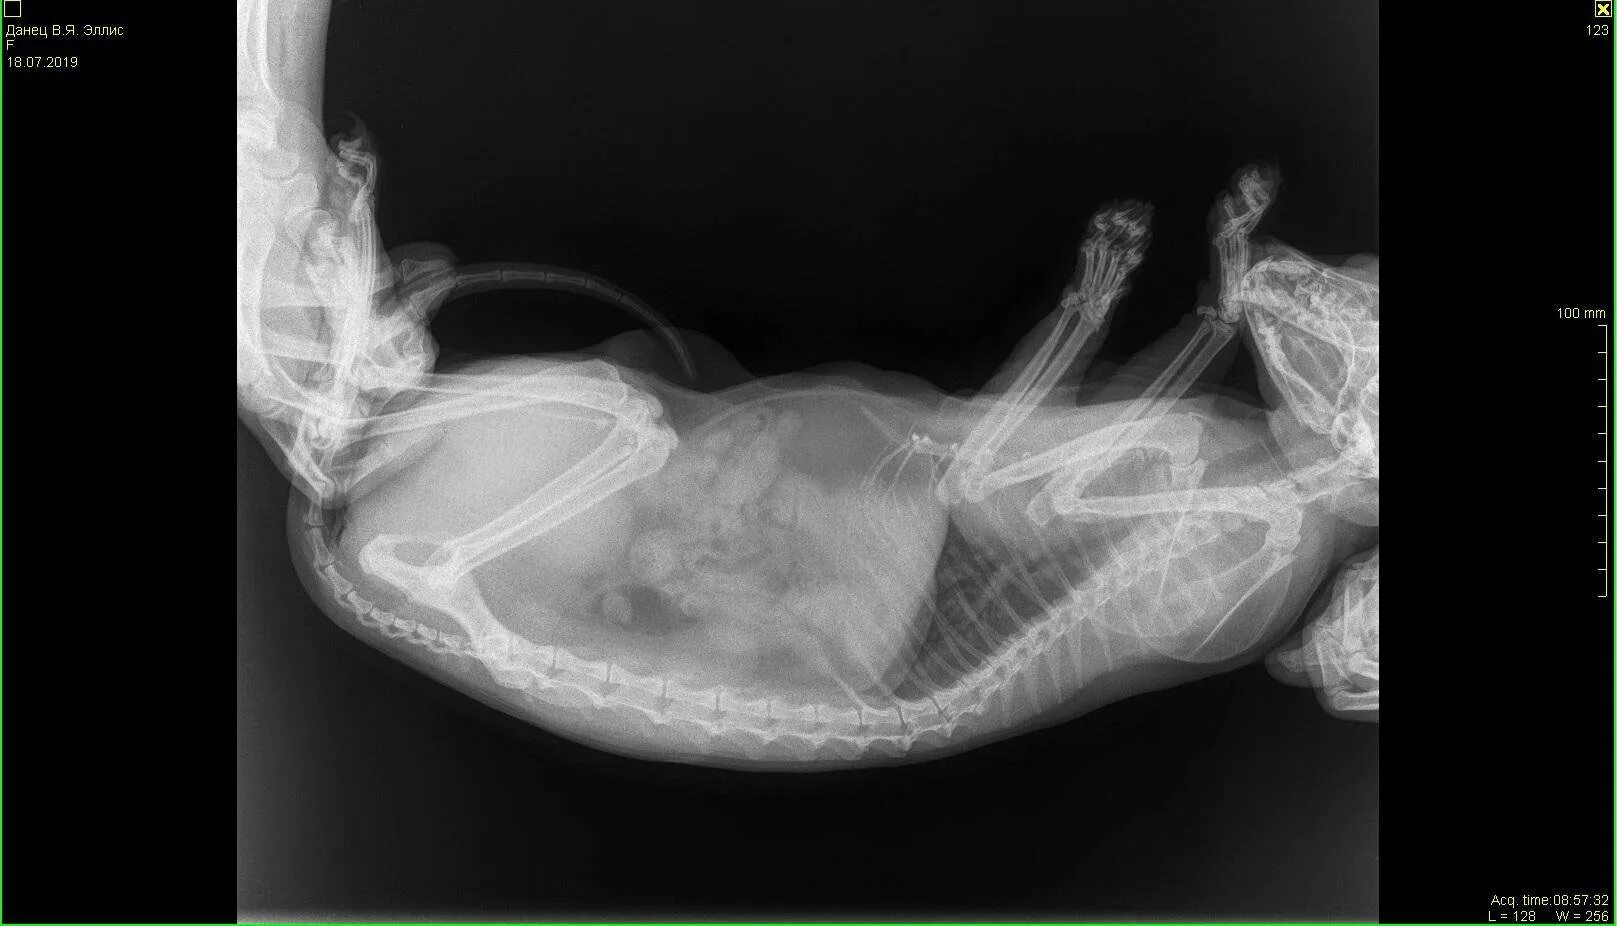

Делала рентген при беременности